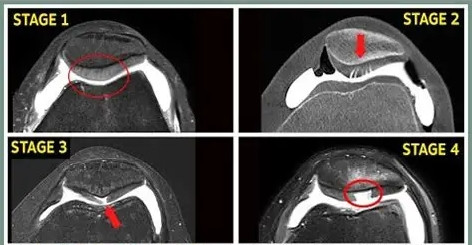

但情况不啻于此,字据严重进度,髌骨软骨问题可分为四级:

●一级:软骨名义软化,轻飘肿胀,像被浸泡过的海绵

●二级:软骨名义出现裂隙和碎屑,但未深及全层

●三级:裂隙加深,造成相通“蟹肉”样的外不雅

●四级:软骨全王人磨损,暴夸耀下方的骨头